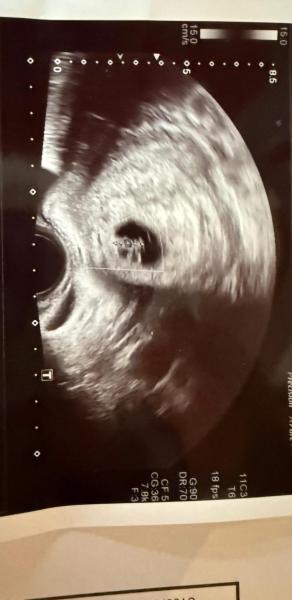

Hi, was meint ihr zu der Ramzi Methode und könnt ihr es erkennen?  wie geht es euch? ❤️ Bild entstand bei 7+6 ❤️

Bild zu Ramzi Methode - Forum für Mai - Mamis

Hallöchen liebe Nessaaa,  ich weiß nicht, wie ich im Mai Forum gelandet bin. Aber das Bild musst du mit der Rundung nach oben drehen.  Dann hast du nämlich ganz schmal unter der Rundung deine Blase und dann deine Gebärmutter. Somit befindet sich das kleine auf der linken Seite und wäre laut Ramzi ein Junge  Liebe Grüße